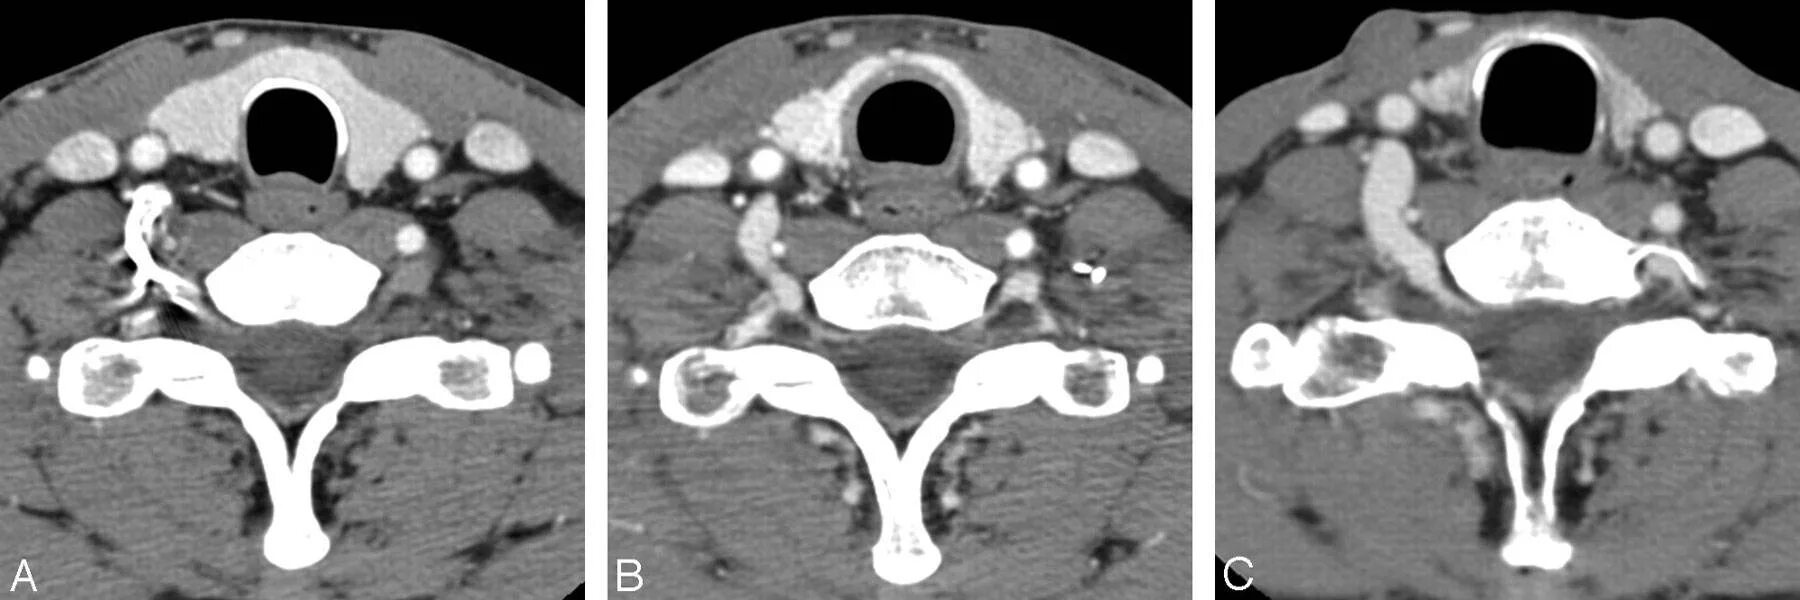

Плохо после контраста кт